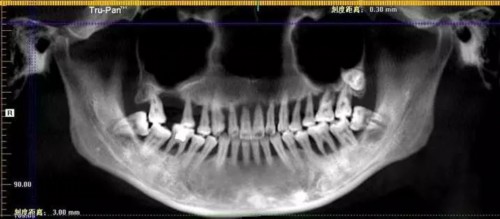

△牙片中清晰可见小萌的上口牙已摇摇欲坠

看过小萌令人震惊的牙片后,细心的人肯定注意到,这姑娘的全口牙虽已不同程度松动,却没有一颗蛀牙。众所周知,口腔卫生不好也是导致蛀牙的主要原因之一,为什么口腔卫生糟到患重度牙周炎的小萌至今没有蛀牙?